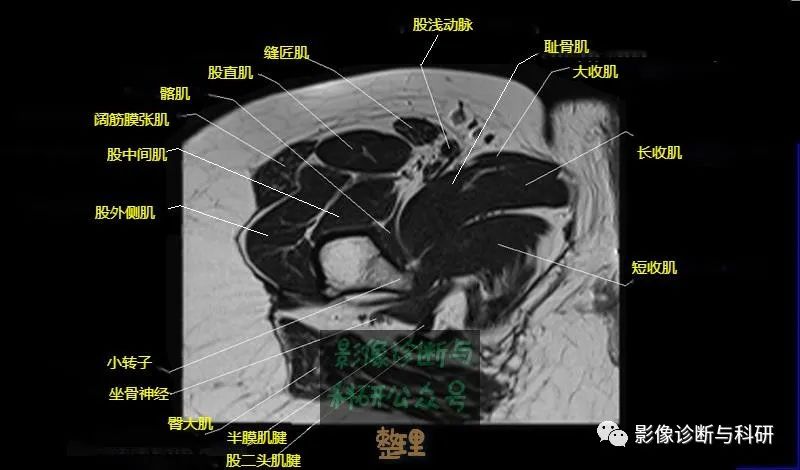

髋关节MR轴位详细标注

大腿肌配布于股骨周围,分前、后和内侧三群

前群

位于大腿前面,有缝匠肌和股四头肌。

内侧群

位于大腿内侧,共5块,其中股薄肌位于最内侧;另4块分三层,浅层靠外上方为为耻骨肌,下方为肌长收肌。长收肌深面是第二层的肌短收肌。第三层是强有力的大收肌。这一群肌均起自耻骨支和坐骨支,除股薄肌止于胫骨上端内侧外,其余各肌都抵止在股骨粗线。

后群

位于股骨后方,包括股二头肌、半腱肌和半膜肌。